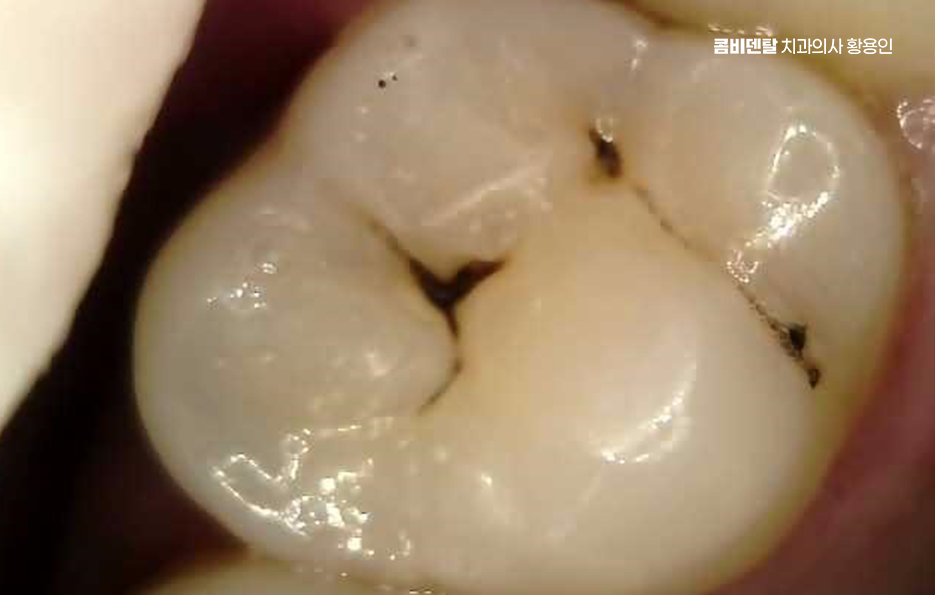

충치 치아 깨짐의 원인부터 살펴보면 대표적인 사례 중 하나는 겉으로 보기에는 작은 충치였던 경우로 치아 표면에 작은 검은 점이 있거나, 음식이 자주 끼는 정도라서 대수롭지 않게 넘겼는데 실제로는 치아 안쪽에서 충치가 넓게 퍼지고 있었던 상황이며 치아는 내부 구조가 약해지면 씹는 힘을 견디지 못하게 되고 그러다 어느 날 딱딱한 음식을 씹는 순간 치아 벽이 무너지듯 깨지는 일이 생길 수 있었어요

특히 어금니에서 이런 일이 자주 발생하는 편으로 어금니는 씹는 힘을 가장 많이 받는 치아인데, 충치가 어금니 씹는 면의 홈을 따라 진행되면 바깥에서는 잘 보이지 않는 경우가 많고 통증도 거의 없어서 치료 시기를 놓치기 쉬울 수 있어요